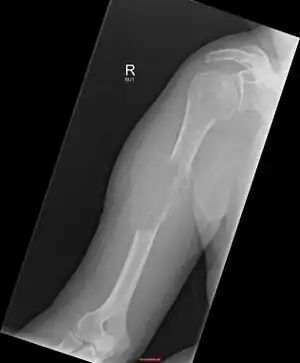

| Solitary plasmacytoma in the long bone of the upper arm | |

1.a. X-ray: solitary plasmacytoma upper arm near shoulder -